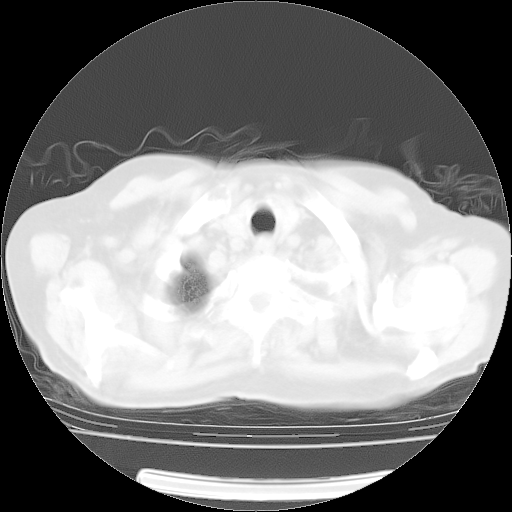

4月14日肺部CT

楼主| 发表于 2010-4-28 16:51 | 显示全部楼层

楼主| 发表于 2010-4-28 16:53 | 显示全部楼层

肺部CT平扫未见异常。